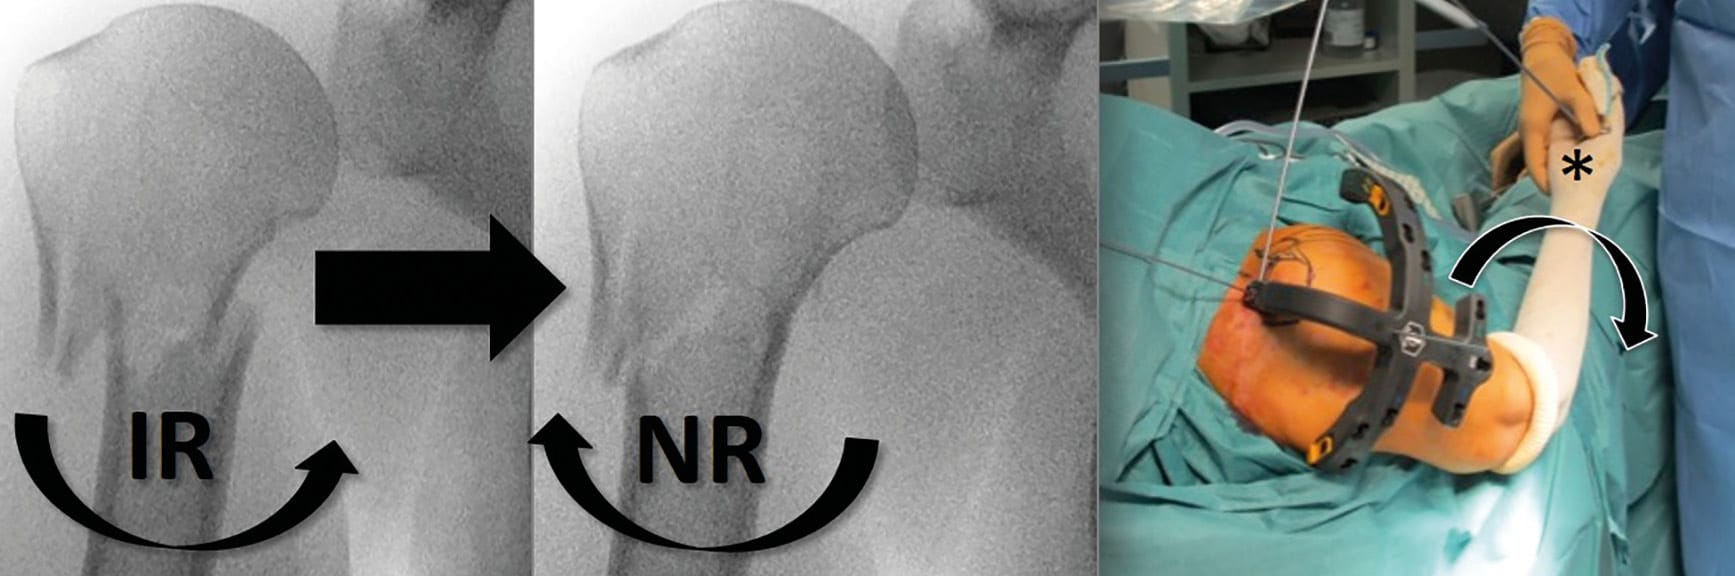

Once adequate guide pin placement is achieved, a 9-mm hole is created in the humeral head using a cannulated reamer. The cannulated nail is placed over the guide wire, inserted at the apex of the humeral head, and then inside the diaphysis, providing appropriate fracture alignment. The arm is placed in neutral rotation to achieve adequate derotation of the humeral diaphysis, whereas adequate rotation of the nail is achieved with the assistance of an external jig aligned with the forearm (Figure 4).

After assessment of the reduction and the nail’s depth under fluoroscopy, the guide wire is retrieved and the two distal screws were first placed in the diaphysis. Once distal fixation is obtained, gentle retrograde impaction of the distal to the proximal segment via a sliding slap-hammer is then performed (“backslap” hammering) to allow intraoperative immediate compression of the fracture site (Figure 5). Finally, proximal fixation is obtained by percutaneous insertion of a minimum of two proximal locking-screws via the attached jig. Postoperatively, the shoulder is placed in a sling for 1 week postoperatively. Passive elbow and shoulder mobilization with pendulum exercises (5 times a day and 5 minutes per session) is performed immediately. Patients are encouraged to remove the brace at day one, and to use their hand for ADLs.